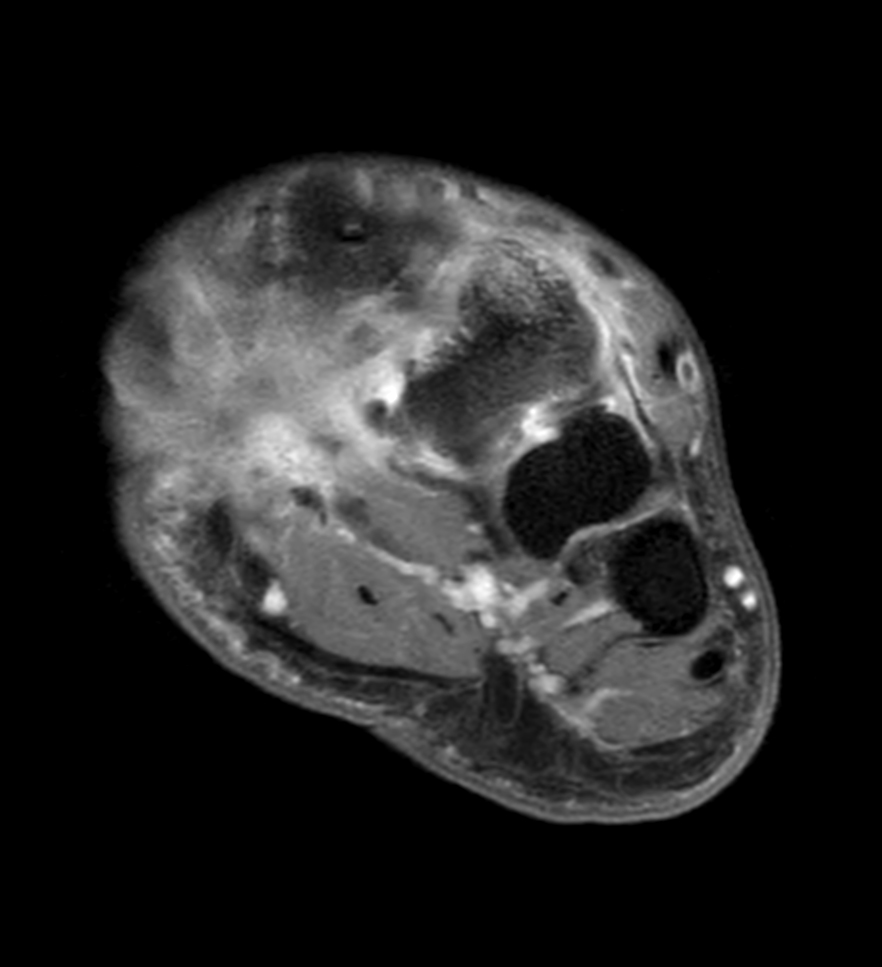

Ankle/Foot imaging post-amputation

Patient with partial amputation of the foot

3D VIEW PDw SPAIR - Axial reformat

Axial T1w mDIXON XD TSE with gado (Water only)

-

Axial T1w mDIXON XD TSE with gado (In Phase)